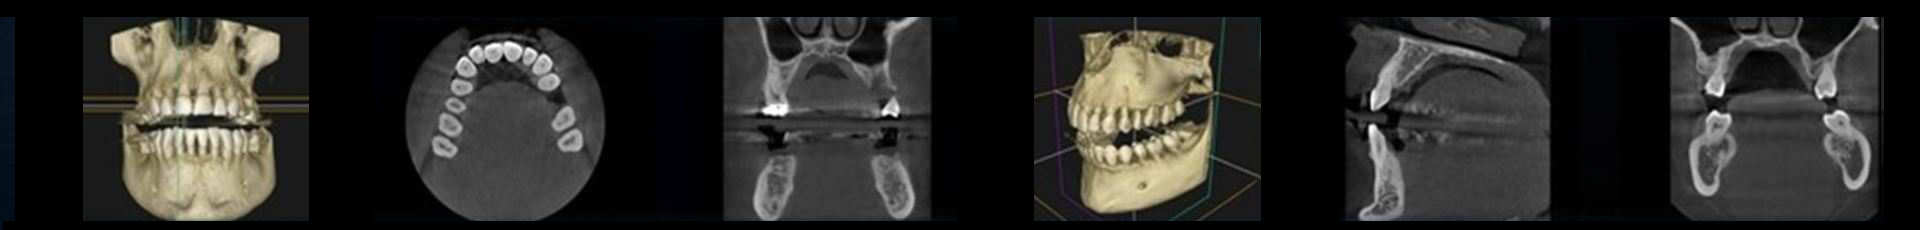

We see our patients in 3D, so it only makes sense to see their teeth that way too. Three-dimensional imaging gives us the best possible view of the patient’s anatomy and, unlike 2D imaging, removes any guesswork or doubt.

A Conebeam CT scan is a type of x-ray that creates 3-D images of dental structures, soft tissue, nerves and bone. It helps guide implant placement and evaluates cysts and tumours in the mouth and face. It can also detect problems in the gum, roots of teeth, and jaws. The Conebeam CT machine rotates around the patient’s head, capturing all data in one single rotation.

Carestream Dental units incorporate all the technologies we need for the best possible results at the lowest dose of radiation by combining high frequency generators, state-of-the-art sensors and image processing. This leads to improved 3D image resolution — up to 75 microns — enabling us to see the smallest details of root and canal morphology. High-precision images give us a more accurate view of our patients’ dental anatomy for improved diagnostics and treatment.